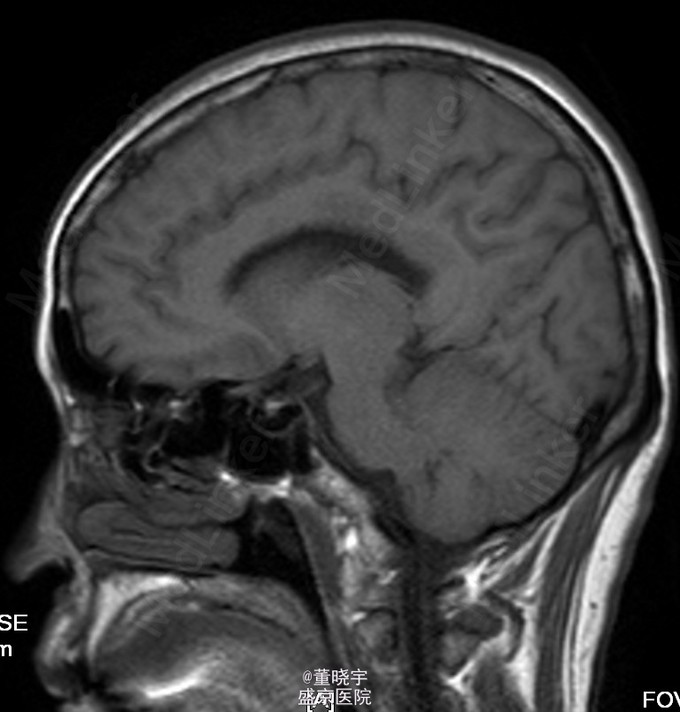

神经系统专科查体:神清语明,双瞳等大正圆,D=4.0mm,对光反射迟钝,视力丧失,双眼球各向运动充分,无复视及眼震,额纹对称,双侧鼻唇沟对称,伸舌居中,转颈有力,四肢肌力Ⅴ级,肌张力正常,双上肢指鼻准确,双下肢跟膝胫试验稳准,BCR L++R++, TCRL++R++,PSRL++R++,Babinski征L+R+,Hoffmann征L-R-,颈强,双掌颏反射(+)。 辅助检查:腰穿压力200mmH2O,细胞总数28*10^6/L,白细胞24*10^6/L,氯化物118.0mmol/L,糖2.41mmol/L,蛋白2.1g/L。 视觉诱发电位:双侧视通路传导障碍。 颅脑MRI见上。 核抗体(ANA)阳性;抗SS-A及抗SS-B抗体均阳性;IgG、IgA升高;补体 C3、C4下降。

诊断:原发性干燥综合征合并中枢损害 处理:静脉点滴丙种球蛋白治疗,临床症状稳定后出院口服强的松片10毫克/天。

半年后患者再次入院复诊,复查颅脑MRI提示新增病灶,但风免相关化验未见改变,急性长期口服激素治疗。 讨论:原发性干燥综合症(pSS)是一种以唾液腺和泪腺腺体淋巴细胞浸润和破坏为特点的自身免疫性疾病,临床主要表现为眼干、口干。腺体外表现主要是由于类似的单核细胞浸润或血管炎引起。CNS-SS的发病率及其颅脑MRI表现目前仍存在争议,有文献报道CNS病变发生率为0%-60%[1]。既往的一个400例患者大样本研究发现,只有1%患者合并CNS并发症。 CNS-SS的临床表现多样,脑部病变包括局灶性和弥漫性病变,局灶性病变主要表现为局部感觉和运动异常、失语、癫痈发作、构音障碍和视觉减退等;弥漫性病变主要表现为亚急性或急性脑病、无菌性脑膜脑炎、心理障碍和认知障碍等。中枢神经系统病变多隐匿起病,少部分患者呈急性或亚急性起病,部分患者同时合并有周围神经系统损害,加上部分pSS患者以中枢神经系统损害为首发症状,使得临床症状表现多样,诊断困难,极易误诊、漏诊并延误治疗。 目前对于pSS合并中枢神经系统病变治疗还没有统一的方案,大剂量激素治疗是目前临床中常用的方法之一,也有报道对于激素效果不佳的患者合并应用环磷酰胺也收到了不错的效果。静脉注射丙种球蛋白(IVIg)也是免疫相关的中枢神经系统病变常用治疗手段之一,尽管外文报道IVIg对于pSS引起的周围神经病变效果明显。